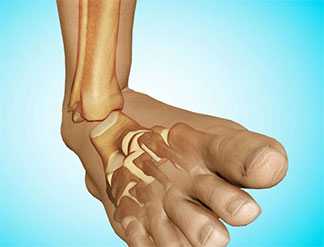

Схематическое изображение нестабильности голеностопного сустава.

Строение голеностопа: кости, сышцы и связки.